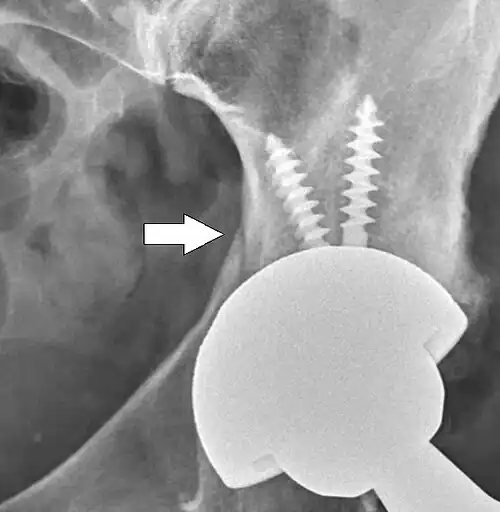

Signs of loosening could either be radiological, clinical or both. Clinical symptoms include pain and loss of function, while radiological signs constitutes migration of the implant or development of radiolucent lines around the implant. The radiolucent lines can be describe using a seven-zone system of the femur described by Gruen et al. and a three-zone system of the acetabulum described by DeLee and Charnley. On radiography, it is normal to see thin radiolucent areas of less than 2 mm around hip prosthesis components, or between a cement mantle and bone. These may indicate loosening of the prosthesis if they are new or changing, while areas greater than 2 mm may be harmless if they are stable.[53] The most important prognostic factors of cemented cups are absence of radiolucent lines in DeLee and Charnley zone I, as well as adequate cement mantle thickness.[54]

Migration pattern can be different depending on the implants and their fixation method (tapered or untapered stem, cemented or uncemented). An early sign of implant failure seems to be if the acetabular cup migrates more than 1 mm within the first two years after surgery. For each additional millimeter of migration, the risk of revision within ten years increases by about 10%.[55]